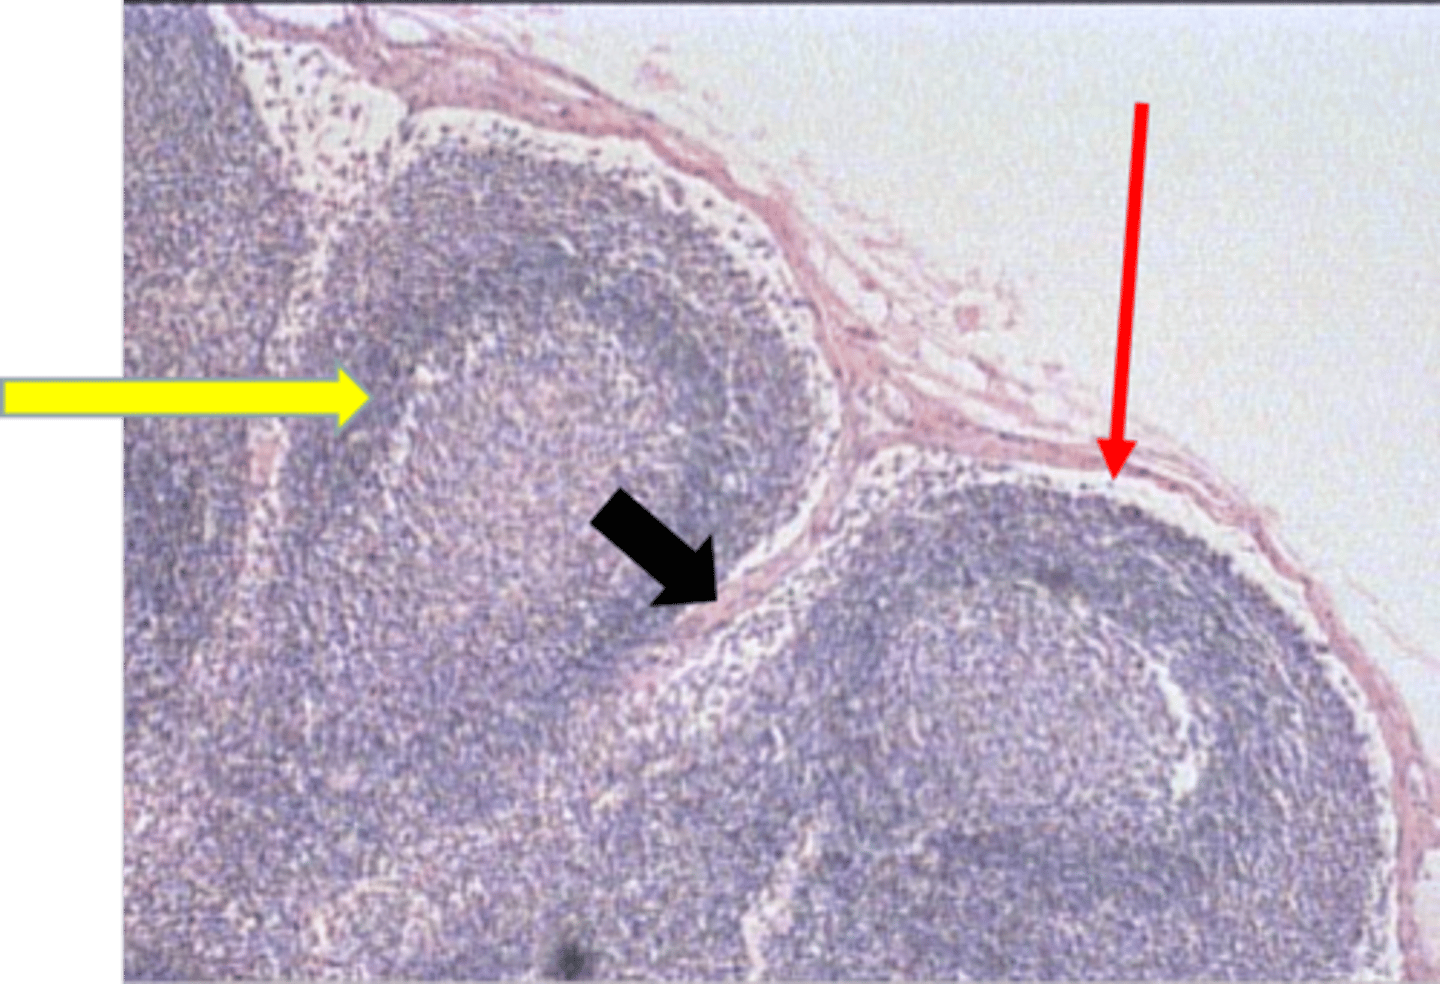

primary lymphatic nodule (made of B lymphocytes)

black arrow

T lymphocytes

red arrow

colon: lymphoid nodule

where is this tissue located?